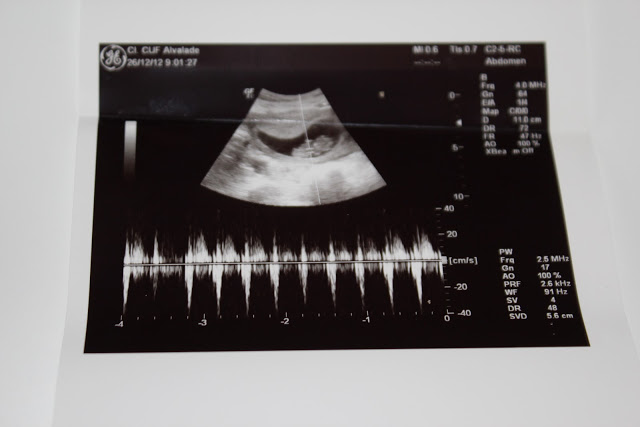

A ecografia de hoje afinal mostrou que ainda faltam quase duas semanas para as 12 semanas, por isso volto daqui a 3 e talvez tenha alguma sorte e fique a saber o que vem desta vez. Uma coisa já ficou definida e vai ser certa. A amniocentese vai ter de ser feita por causa da minha idade, mas como desta vez o aviso foi feito com alguma antecedência, o choque não foi igual, aliás não houve choque algum, vai ser mais um exame, mais chato, mas que vai correr bem…

Muitos parabéns, é necessário coragem para o 3º filho, com 2 princesas ainda pequeninas. Mas com amor e muita organização tudo se faz. Eu tive que fazer amiocintese e não custou absolutamente nada, só senti uma pressão na barriga, nada de dor, nada mesmo, pois a agulha que utilizam é extremamente fina. Também foi super rápido e depois é mais uma oportundade de "ver" o bebé, já que tem que ser feito com uma ecografia. Vai tudo correr bem. As decorações são lindas, eu também se pudesse mudava tudo, vou-me entretendo a fazer colchas e cortinas para os quartos, mas os móveis são sempre os mesmos. Desejo-vos um excelente 2013! bjs